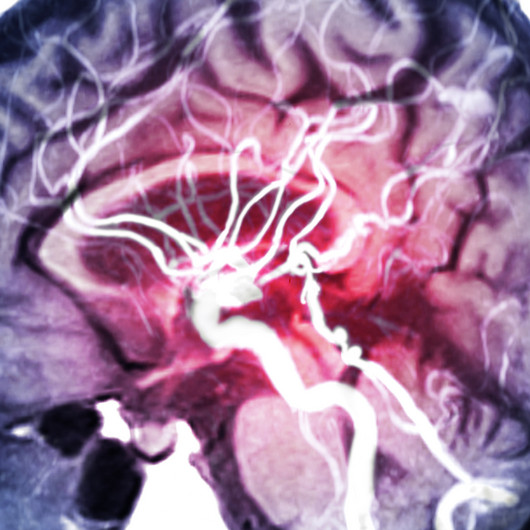

Bei großen Blutgerinnseln reicht die Thrombolysebehandlung oft nicht aus. In diesem Fall und auch wenn die Thrombolyse aus anderen Gründen bei einem Patienten nicht durchführbar ist, ist die Thrombektomie eine moderne und hochwirksame Methode der Schlaganfallbehandlung. Mit einem Katheter kann die Durchblutung einer verschlossenen Arterie im Gehirn minimalinvasiv wiederhergestellt werden. Dabei wird ein Katheter über die Leistenarterie bis in das betroffene Hirngefäß vorgeschoben und an der betroffenen Stelle platziert. Der Thrombus verfängt sich in dem Gittergeflecht des eingeführten Stent Retrievers und kann schonend aus dem Gefäß herausgezogen werden. So wird das Gerinnsel entfernt, der Blutfluss wiederhergestellt und Hirngewebe revitalisiert. Der Eingriff erfordert eine hohe medizinische Expertise. Unsere Experten der Radiologie führen ihn in Zusammenarbeit mit dem Team der Stroke Unit erfolgreich durch.